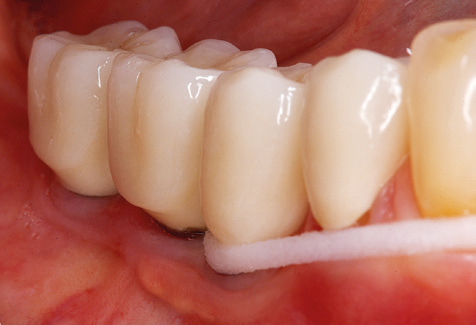

Following machine cleaning of the tooth and implant surfaces, the surfaces of the natural teeth are cleaned manually using standard hand instruments. When performing manual cleaning, particular attention must be given to maintaining the correct angle of application, appropriate sharpness, good support and working with the curette from apical to coronal. Either titanium or carbon curettes should be used for post-cleaning of the implant structures (Fig. 8). In addition to the use of ultrasonic devices, power jet devices can also be used in conservative dentistry. However, it must be taken into consideration that these procedures are not suitable for removing hard deposits and thus they cannot replace the use of hand instruments and ultrasonic instruments completely. In all cases, cleaning is followed by mechanical polishing of the accessible tooth and implant surfaces with polishing cups and polishing compounds (Fig. 9).